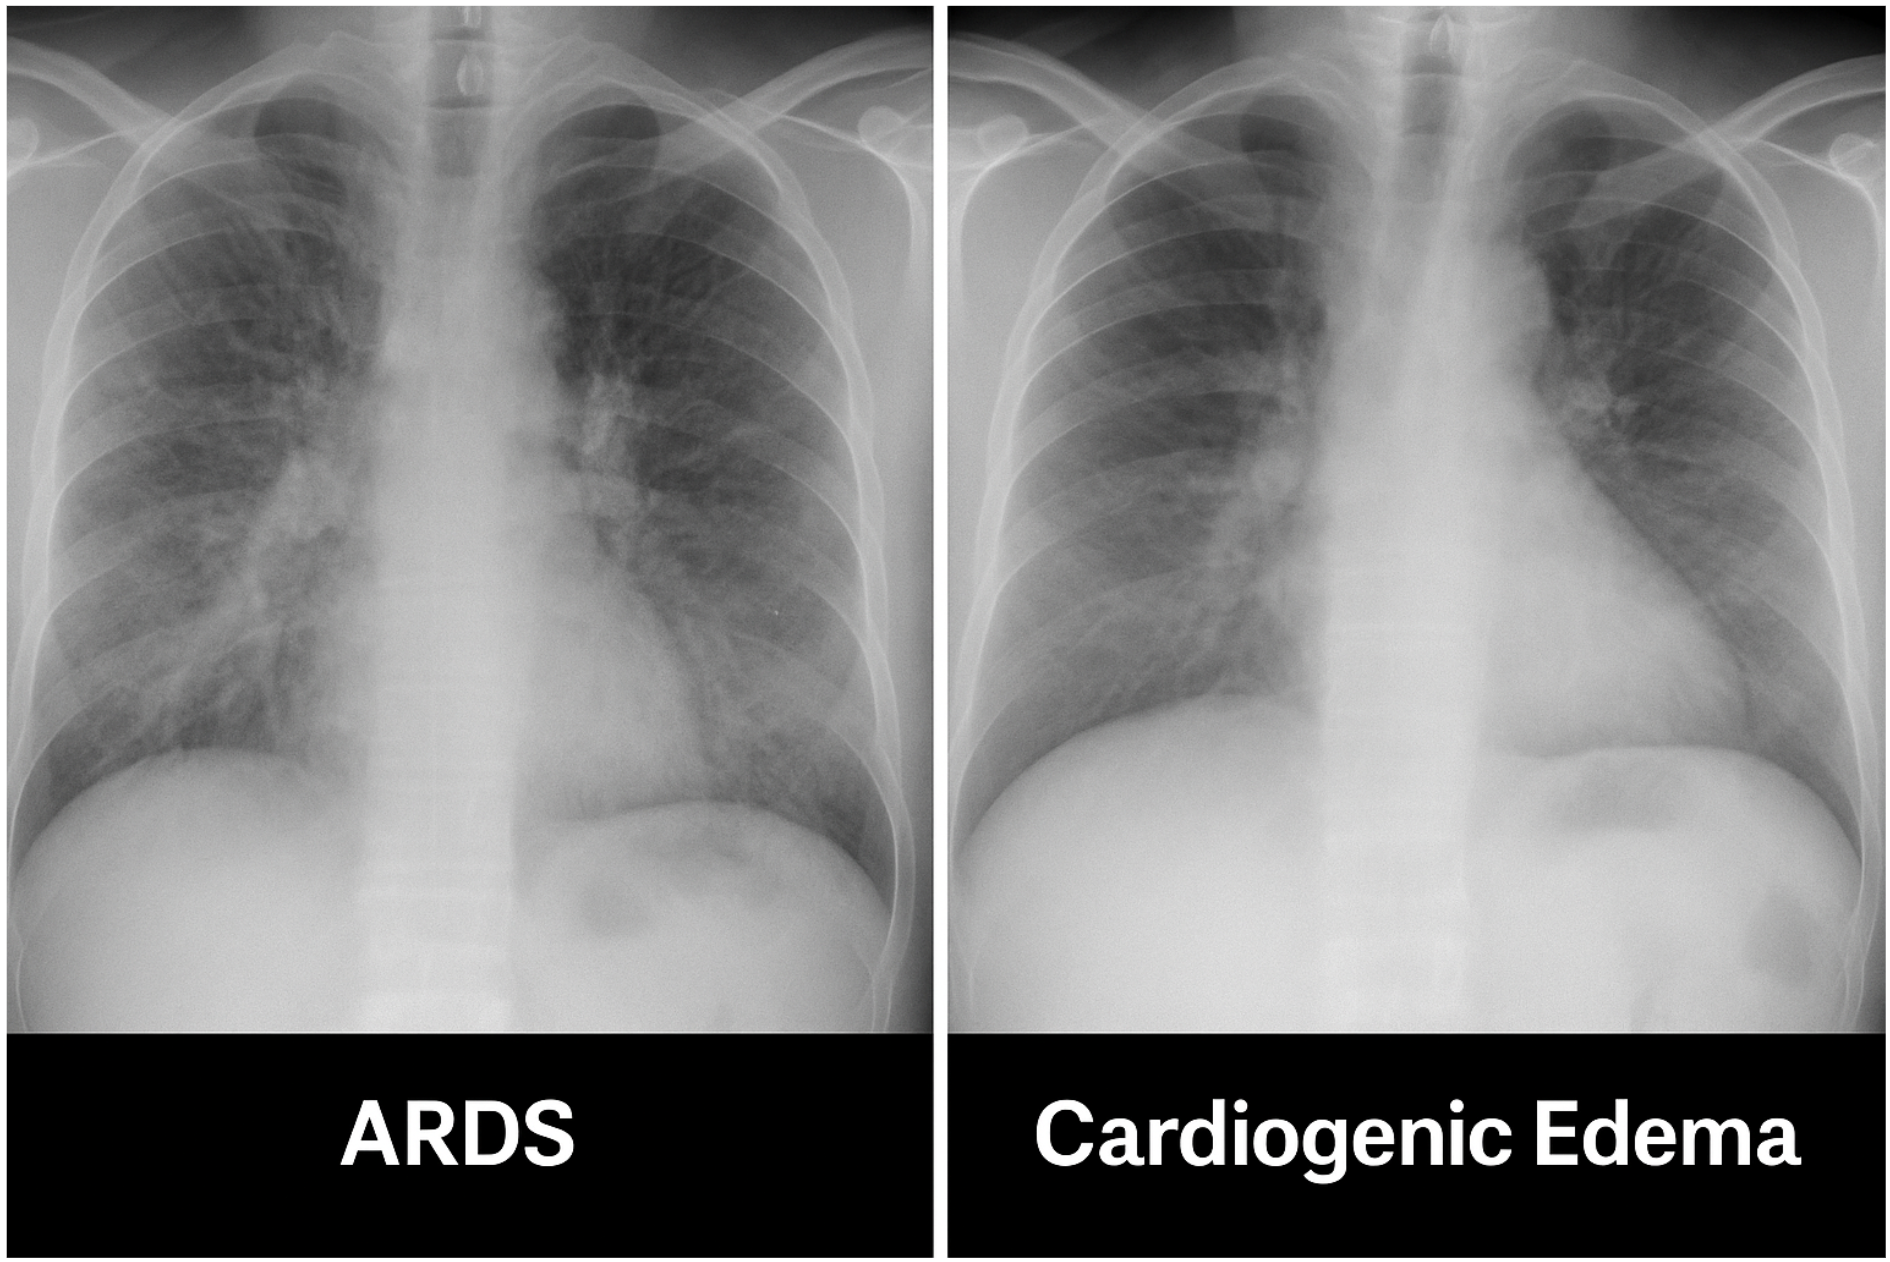

⚠️ How to Differentiate ARDS from Cardiogenic Pulmonary Edema

| Feature | ARDS | Cardiogenic Edema |

|---|---|---|

| Onset | Acute (hours–days) | Acute or chronic exacerbation |

| LV function (Echo) | Often preserved | Usually reduced |

| BNP | Normal or mildly ↑ | Markedly ↑ |

| PCWP (if monitored) | < 18 mmHg | > 18 mmHg |

| BAL | Neutrophils, proteinaceous fluid | Clear transudate |